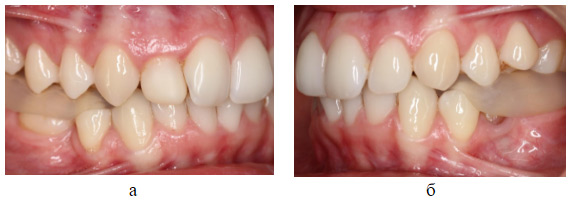

По результатам ТЭНС изготавливалась разобщающая зубные ряды каппа для постоянного использования, исключая время приема пищи и гигиенических мероприятий (Рис. 2,3).

Рис.2. Разобщающая каппа, вид с правой (а) и левой (б) сторон.

Рис. 3. Разобщающая каппа, приоткрытый рот.